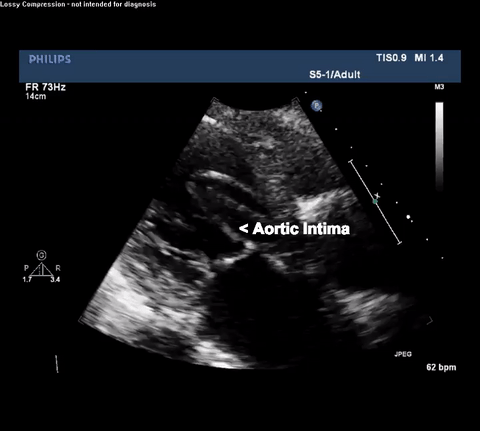

Type A acute aortic dissection (TA-AAD). Cardiac POCUS imaging in the

parasternal long axis revealed the intima of the ascending aorta undulating in

and out of the left ventricular outflow tract throughout the cardiac cycle,

consistent with a TA-AAD.

TTE Parasternal Long Axis View

CT Thorax with angiogram